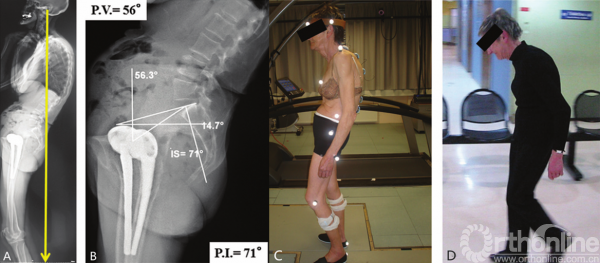

图3-40 行走时,由于臀大肌无法维持骨盆后倾,矢状位失平衡加剧

图3-41 A.静态后方失平衡患者;B.PI角大,后倾代偿幅度大的患者;C.步态分析;D.患者行走过程中伴有严重的矢状位失平衡

行走评估

整个脊柱的静态X线片并不代表运动过程中的真实状态。Lee等[29]研究表明,与静态侧位图像相比,术后平背患者行走时的前倾失平衡更为明显。一个可能的解释是,由于臀大肌肌肉力量减弱,在行走时不能够维持骨盆极度后倾状态。代偿现象在静态研究中起到了很大的作用,但并不能在动态研究中起到作用[30]。

有些患者存在过度后倾失平衡,表现为他们觉得“坐在自己的骨盆上”,外耳道铅垂线落在股骨头后方,行走时躯干向前倾斜。腰椎截骨术可以极大改善这些患者的状态(图3-40)。